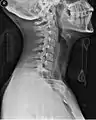

Side view X-ray of the neck with a cervical collar